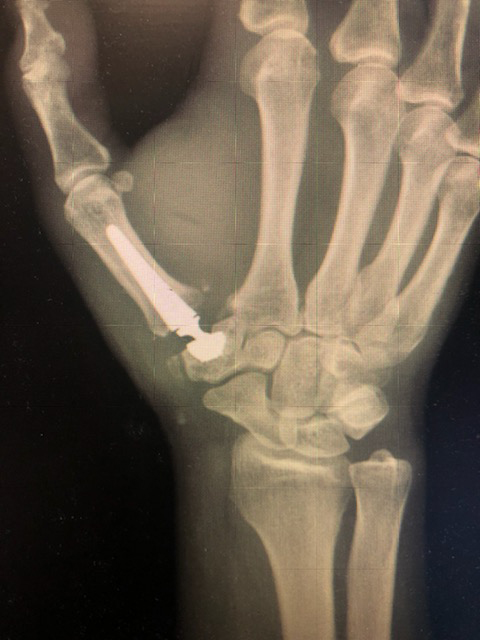

Spośród bardzo szerokiej gamy realizowanych świadczeń medycznych nasi specjaliści wykonują również zabiegi nowatorskie, a jednym z nich jest endoprotezoplastyka stawu śródręczno-nadgarstkowego kciuka. Wskazaniem do wykonania tego typu zabiegu była choroba zwyrodnieniowa stawu, która objawiała się u pacjenta znacznym bólem u podstawy kciuka utrudniając codzienne funkcjonowanie. Dzięki wykonanemu zabiegowi przez lek. med. Włodzimierza Witwickiego przy asyście lek. med. Jacka Piątka, polepsza się ruch w stawie, ustępują dolegliwości bólowe oraz generalnie poprawia się komfort życia.